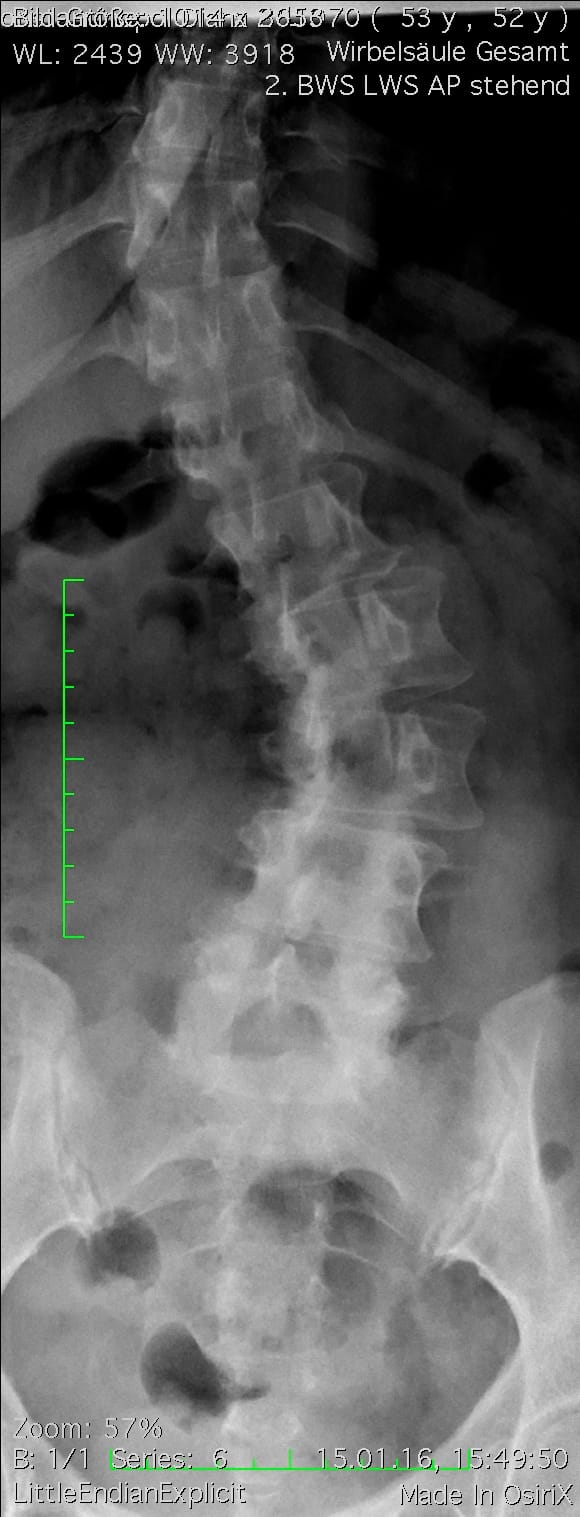

Torsional scoliosis of the lumbar spine measuring 40° (left image) Dynamic corrective spondylodesis with flexible carbon fixator (right image)